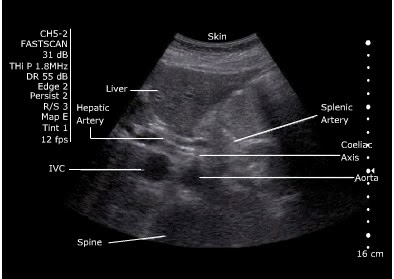

Abdominal Aorta Ultrasound

I'm rubbish at aorta ultrasounding, and it's one of the few scans that might actually be useful in the ED. I've done my level one course...but it was a while ago, and honestly...I can't remember what I'm looking for anymore. I've written this to try and remind myself...

Anatomy

Xiphoid, through until umbilicus (fourth lumbar vertebra)

- Coeliac axis is 1-2 cm below the diaphragm

- Superior mesenteric artery is 2 cm below the coeliac axis

- Inferior mesenteric artery is 4 cm above the bifurcation

Diameter - <2cm = normal, 2-3cm dilated but not aneurysmal, >3cm aneurysmal

- Start underneath the xiphisternum and identify the aorta - look for the vertebral body just behind it, liver anteriorly and bowel to the right.

- Make sure you are not looking at the IVC.

IVC: Right side, thin walled, compressible, transmitted pulse (‘double bounce’), almond shaped, shape varies

Aorta: left side, thick walled, will not compress, pulsatile, round in shape, constant shape

- Look for the coeliac axis. This is high and often difficult to see. It divides into splenic and hepatic artery - said to resemble the wings of a seagull. This is not essential to find.

- Sweep to the umbilicus

- Move the probe longitudionally and scan.

- Look for the "snowman" - where the SMA comes off at the coeliac trunk

Measure

Outer wall to outer wall.

No oblique or angled cuts